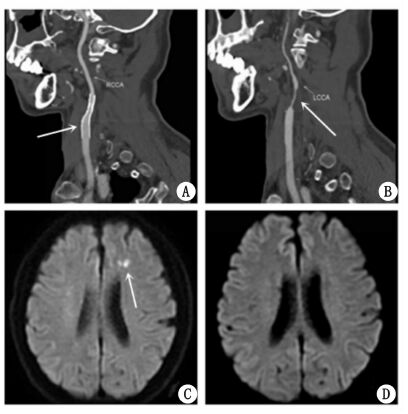

CAS术后1个月,患者因突发右侧肢体无力再次急诊就诊本院。入院查体显示患者右上肢肌力Ⅱ级,右下肢肌力Ⅲ级,左侧肢体肌力较前次住院无明显变化。复查颈动脉CTA显示原右侧颈内动脉支架位置良好,管腔通畅(图 2A)。左侧颈内动脉再通,管腔呈重度狭窄,狭窄率约90%(图 2B)。而头颅磁共振显示左侧额叶多发新鲜梗死灶(图 2C)。结合影像学检查结果,笔者认为患者左侧急性脑梗死为左颈内动脉自发性再通引起斑块脱落所致,建议患者1个月后行左颈内动脉支架植入术,但患者拒绝。故患者病情稳定后出院,继续药物保守治疗。目前患者随访16个月,未再发脑卒中及TIA。

| 图 2 患者颈动脉支架植入术后复查颈动脉CTA(A、B),术后头颅MRI弥散加权图像(DWI)(C),术前同一患者头颅MRI弥散加权图像(DWI)(D) |